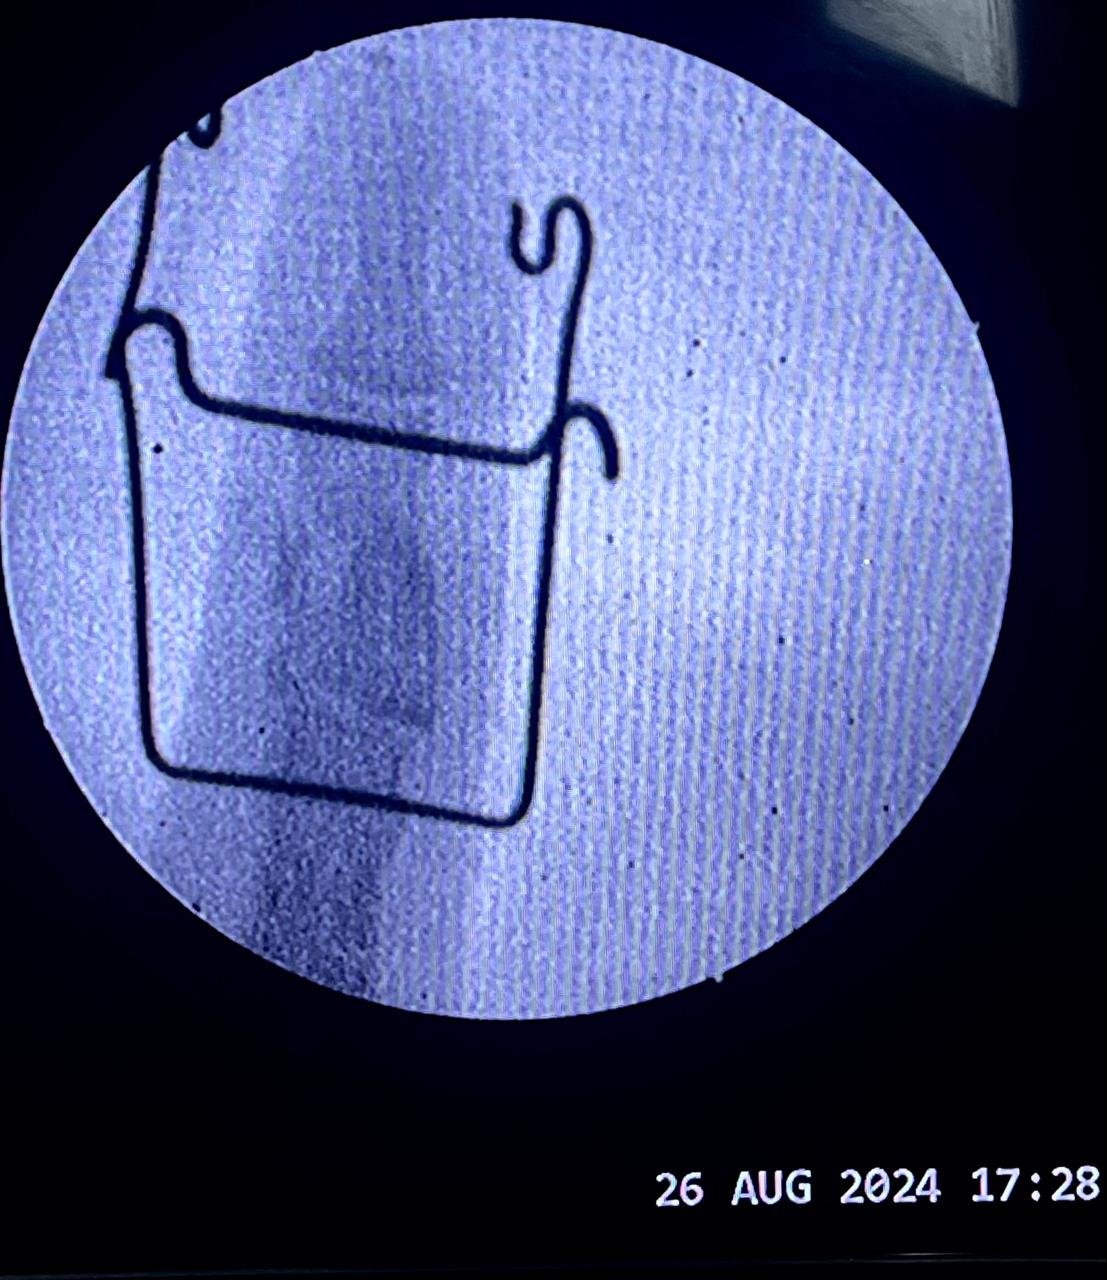

& fibula | Heal fracture pre & postop | Clavicle

fracture pre &

Heal fracture pre & postop | Clavicle fracture pre &